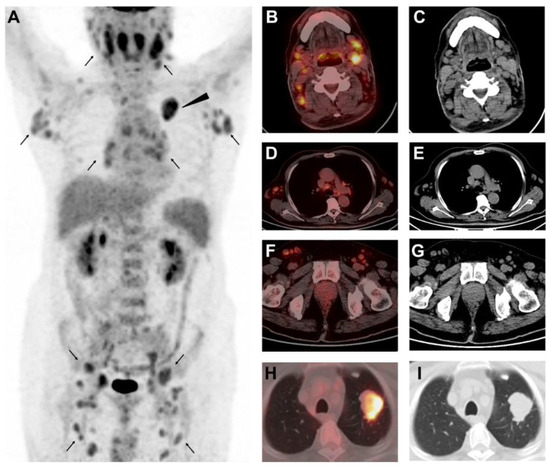

Different Uptake of 68Ga-FAPI and 18F-FDG in Lymphadenopathy Caused by Angioimmunoblastic T-Cell Lymphoma in a Patient with Colon Cancer

Wu, M.; Pan, Q.; Luo, Y. Different Uptake of 68Ga-FAPI and 18F-FDG in Lymphadenopathy Caused by Angioimmunoblastic T-Cell Lymphoma in a Patient with Colon Cancer. Diagnostics 2022, 12, 2211. https://doi.org/10.3390/diagnostics12092211